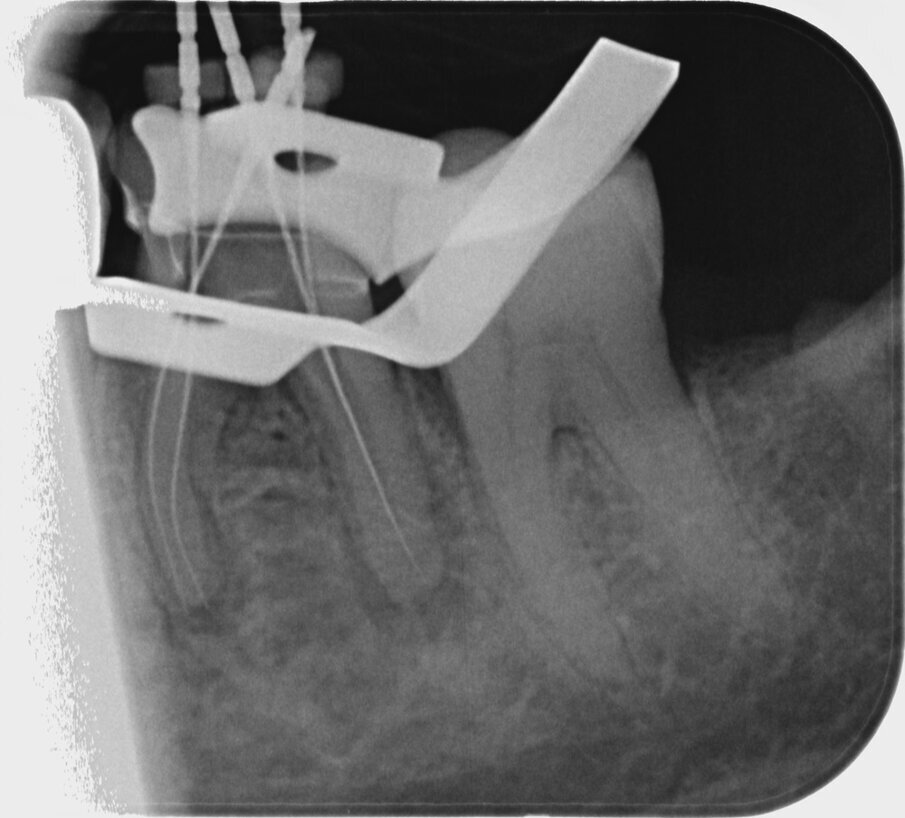

An 87-year-old female patient was referred to our clinic with pain in the third quadrant. The clinical and radiographic examination (using single-image radiography and CBCT) confirmed the suspicion of symptomatic periapical periodontitis at tooth #36 (Fig. 1). The preoperative single image suggested that a carrier-based root canal filling material had been used; furthermore, two ledges were visible in the mesial canal system. In addition, a second distal canal had to be assumed.

The remaining apical gutta-percha was removed distally using a reciprocating 25/.06 MicroMega One RECI (Fig. 6). Owing to its cross-sectional design, this instrument features high cutting performance, making it ideal for revision treatment.

The corresponding NiTi files were then used for renewed preparation of the root canals. Normally, in the presence of ledges, I prepare a glide path with manual instruments as a standard procedure. In this case, the use of prebent rotary instruments eliminated the need to create a manual glide path. In this case, the mesial ledges were bypassed by alternating between a 15/.03 HyFlex EDM and a 10/.05 HyFlex EDM. At the same time, the non-instrumented canal sections were developed. The second distal canal, which had not been treated during initial treatment, was instrumented with these two files in the same manner as the preparation of the mesial canals. Here too, the advance creation of a manual glide path could be dispensed with.

After preparation of the glide path, the following HyFlex EDM sequence was used: first the 20/.05 instrument, then the 25/~ HyFlex EDM OneFile and finally the 40/.04 file in all canals (Figs. 7–10). An acoustic signal from the endodontic motor indicated when rinsing should ideally be performed to remove the abraded debris from the canal. Obturation was performed with a bioceramic sealer (BioRoot RCS, Septodont) using the single-cone technique (Figs. 11–13). The contrast image with the master points and the final radiographic check after obturation demonstrated preservation of the canal anatomy and maintenance of the original path of the canal (Figs. 14–16).

Fig. 7: Preparation with the 20/.05 file in the canal.

Fig. 8: Preparation with the universal OneFile in the canal.

Fig. 9: Final preparation distally.

Fig. 10: Final preparation mesially.